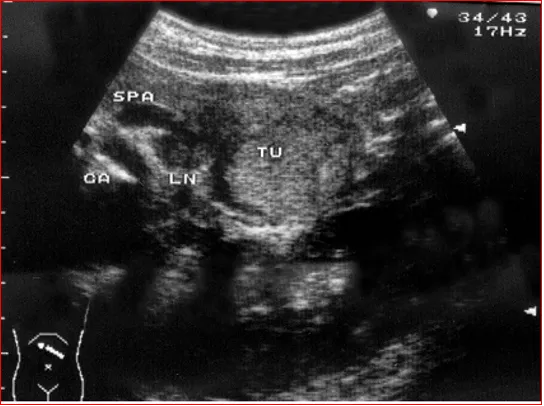

恶性胰岛细胞瘤,伴淋巴结肿大

恶性肤岛细胞瘤一般体积较大,形态不规则,常有局部浸润或肝、脾、淋巴结转移声像图表现;CDFI示内部血流信号丰富,坏死液化内无血流信号。

● 无功能胰岛细胞瘤:直径<5cm的肿瘤多为圆形均匀低回声,边界清,有包膜。大的肿瘤呈类圆形、分叶状或不规则,呈低或混合回声(病灶坏死液化或钙化),胰腺变形,并挤压邻近血管脏器。

● 胰岛素瘤:多为边界清、圆形、均匀低回声,CDFI示内部血流信号丰富。

超声检查